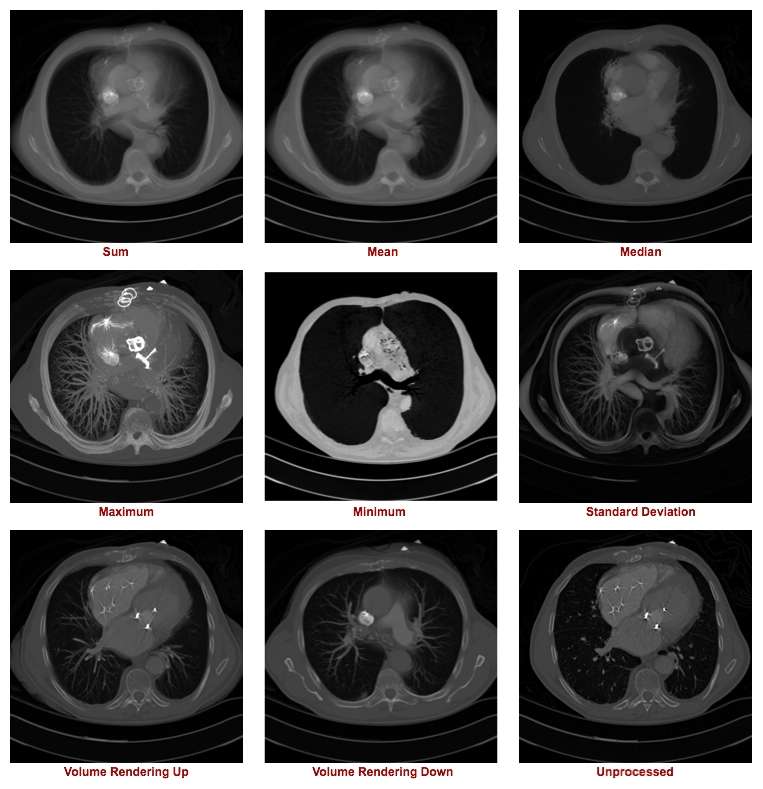

The first technique we'll consider is a relatively simple one called Axial Projection. It involves integrating a number of axial images to display a composite which presents a three-dimensional impression of that volume of image data. The technique is sometimes referred to as Thick Slab or Z-Projection.

The figure below illustrates the outcome of a range of z-projection methods, with a single slice shown in the bottom right hand corner for reference purposes. The first image in the top left shows the result of summing 16 slices, and the other two images on that row show the results of computing the mean and median of these slices.

The first two images in the second row show the result of what are called a Maximum Intensity Projection (MIP) and a Minimum Intensity Projection (MinIP), respectively. A MIP evaluates each voxel along each line of voxels through the volume to determine the maximum voxel value and forms an image using the values so determined for each line. A MinIP uses the minimum voxel values, as illustrated in the following figure:

Volume rendered projections are shown in the first two images along the bottom row of our collection of example axial projections. This image compositing method involves applying an opacity function to the voxel data as well as a recursive addition of the resulting data. An equation of the form:

The outcome of this form of processing is the generation of an image which includes visual depth cues on the basis that similar voxel values will be displayed with a similar transparency and those closest to the reference slice having a stronger contribution than those from more distal slices. Further, note that all voxel values in each line contribute to the rendered image, in contrast to the limited number of voxels that contribute to a MIP or a MinIP image. A 3D effect results from volume rendering, as illustrated in the images above.

Notice that volume rendering can be applied from distal to proximal slices, as illustrated in our figure, as well as in the opposite direction, i.e. from proximal to distal slices. Hence the terms Volume Rendering Up and Volume Rendering Down used in our set of nine example images above.

The type of axial projection method appropriate to an individual patient study is dependent on the anatomical and/or functional information of relevance to the diagnostic process. Let's take the case of imaging contrast-filled blood vessels, for example, in our nine example images above. Note that a MIP can be used to give a visually-stunning impression of the vessel bed in the patient's lungs. There's little depth information in this projection, however, so that overlapping and underlying vessels can obscure lesions that might be present in blood vessels of interest. The application of this form of axial projection to angiography is therefore limited to studies where vessel overlap isn't an issue. The inclusion of voxel transparency and depth weighting in volume rendered images addresses this limitation of MIP processing.